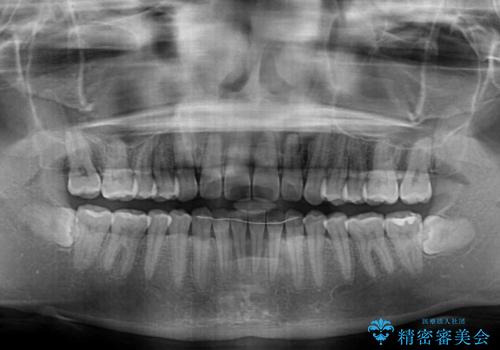

すきっ歯はあっという間に後戻りを起こすので、可及的に後戻りを防止するために、上下前歯部を舌側からワイヤーで固定しています。

通常は下顎前歯のみに行っていますが、空隙歯列弓では上顎でも行っています。